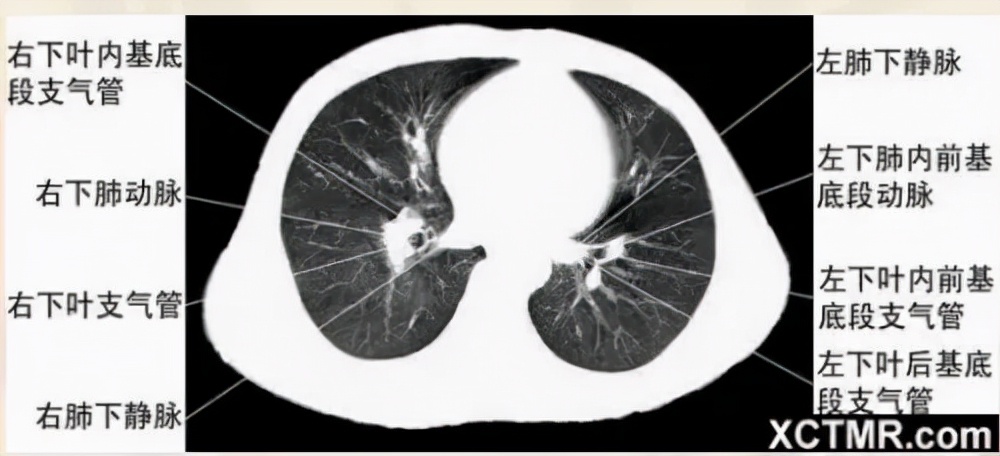

右基底支气管层面